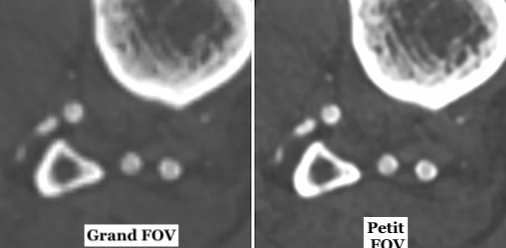

Il s’agit plus globalement d’évaluer l'impact du champ de vision reconstruit (FOV) sur la qualité de l'image en angiographie par tomodensitométrie (CTA) des membres inférieurs. Pour cette étude, un total de 100 examens CTA des membres inférieurs ont été acquis sur un scanner multidétecteur 2 × 192 coupes. Trois ensembles de données différents ont été reconstruits couvrant les deux jambes (taille FOV standard) ainsi que chaque jambe séparément (taille du

FOV réduite). La qualité subjective de l'image a été évaluée pour les différents segments de vaisseaux (fémoral, poplité, crural, pédieux) par trois lecteurs à l'aide d'une échelle de Likert semi-quantitative. De plus, la qualité d'image objective a été évaluée à l'aide d'une métrique de qualité d'image automatisée pour chaque coupe.

Une reconstruction séparée des deux membres inférieurs aboutit à une meilleure qualité des images

L'évaluation subjective de la qualité de l'image a montré une concordance presque parfaite entre les évaluateurs. La qualité d'image obtenues à partie des petits FOV a été notée significativement plus élevée par rapport aux grands FOV, pour tous les patients et segments de vaisseaux, avec une différence plus nette pour les petits vaisseaux. La différence des scores moyens entre le groupe grand FOV vs petit FOV était de 0,68 pour le niveau fémoral, 0,83 pour le niveau poplité, 1,12 pour le niveau crural et 1,08 pour le niveau pédieux. La métrique objective de la qualité de l'image a également démontré une amélioration significative de celle-ci dans les ensembles de données relatives aux petits FOV.

Les chercheurs en donc conclu que la reconstruction latérale séparée de chaque jambe dans le CTA des membres inférieurs à l'aide d'un petit FOV de reconstruction améliore considérablement la qualité de l'image par rapport à une reconstruction standard avec un grand FOV couvrant les deux jambes.